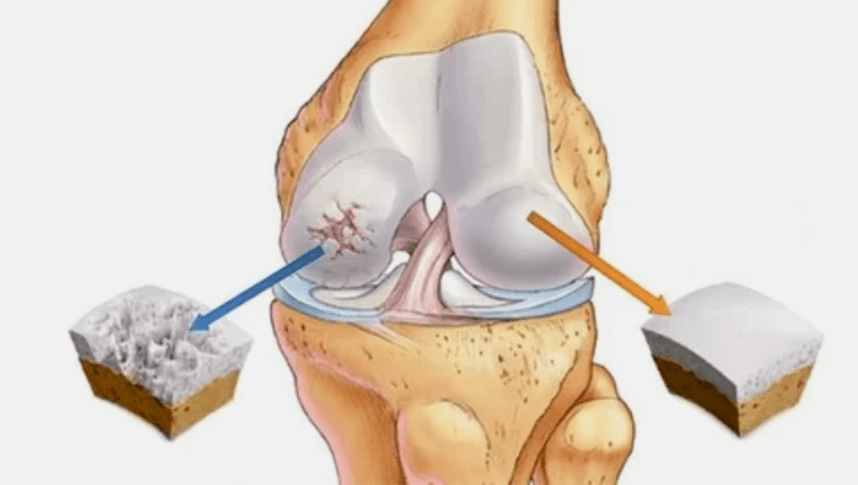

- Hyaline coating pathologies.Cartilage thinning leads to replacement of its pathological tissues - bone structures.

- Anomalous growths appear in cartilage - osteophytes.

- The violation that emerged from the natural anatomy of cartilage and bones causes the overload of healthy areas of the cartilage.The destruction of untreated joint tissues is constantly progressing and leads to incapacity.

When the degree of disease increases, pathological processes are still aggravated.In the end, all Hyalin's cartilage is destroyed.